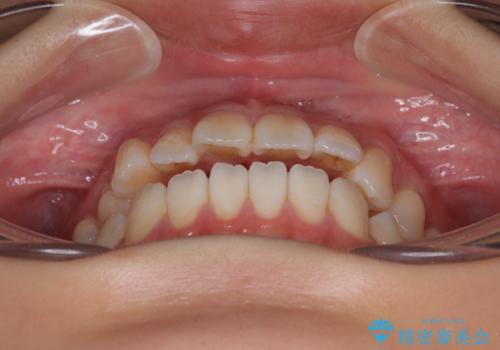

舌の突出癖が原因 インビザライン矯正による開咬改善

- 前歯の開咬を気にして来院された患者様です。

開咬の治療は、前歯を閉じるように動かすとともに、上下臼歯を圧下(骨内にめり込ませる)させることで進めて行きます。

オープンバイトは舌の突出癖により誘発され、治療後も突出癖が残っている容易に後戻りしてしまいます。

治療期間を短縮するためにも、舌突出癖の改善が極めて重要となります。

特にインビザラインではIPRという歯と歯の間を削る処置を多用するため、後戻りによりスペースが生じやすくなるため、治療初期段階での舌のトレーニングが必須となります。